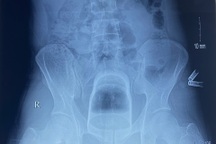

Qua thăm khám, bác sĩ phát hiện dị vật nằm sâu trong trực tràng cách rìa hậu môn 8-10cm. Khai thác bệnh sử, trước đó do bắt chước các clip đăng tải trên mạng, bệnh nhân tự ý nhét củ cà rốt vào hậu môn để thử cảm giác lạ. Nhưng nhét xong, bệnh nhân không thể lấy củ cà rốt ra và đau nhức nặng nề nên đến Bệnh viện Vạn Phúc 1 (tỉnh Bình Dương) cầu cứu.

Để xử trí cho bệnh nhân, các bác sĩ đã tiến hành gây mê và lấy thành công dị vật là củ cà rốt có đường kính khoảng 4cm, dài 20 cm.